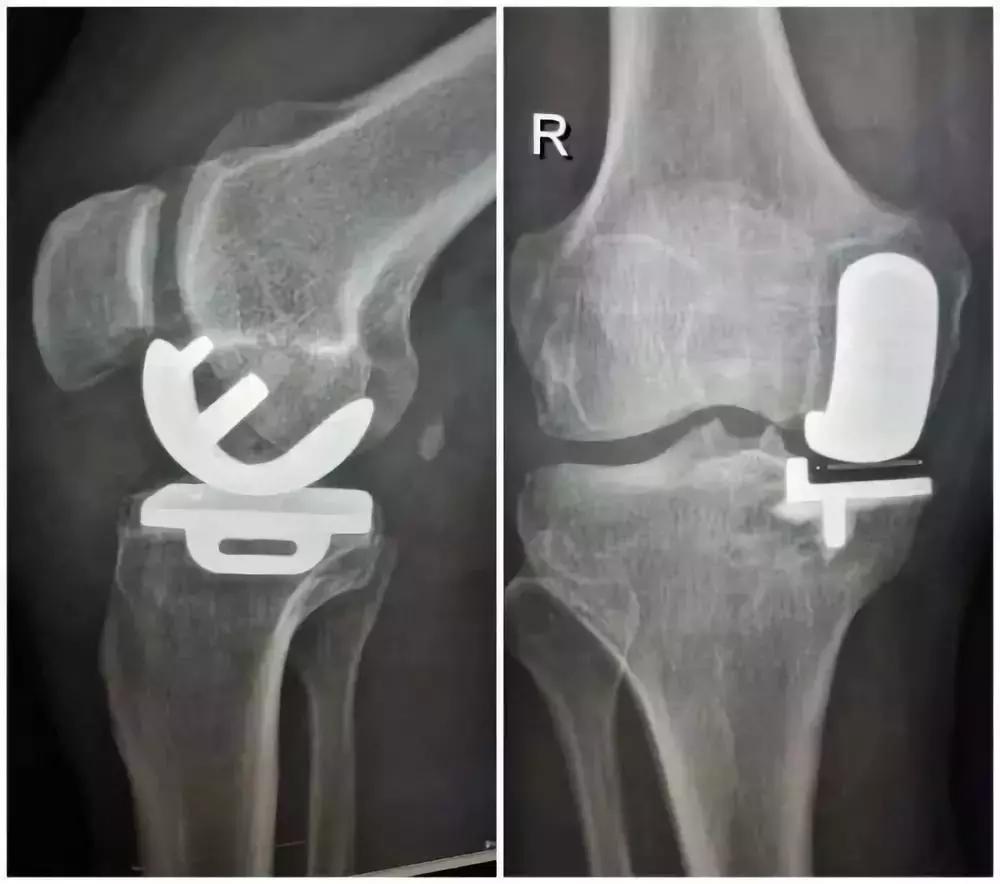

还有一种手术,我认为更好,但需要掌握时机,这就是单髁置换术!

单髁置换术,可以阻断骨性关节炎的恶性循环进展,让患肢恢复正常功能!

一些患者的术后几天就可以扶助行器走路的情况!